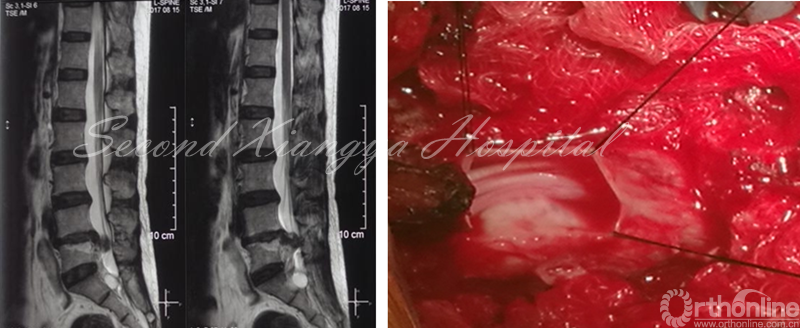

F,46岁,L4/5 LDH,外院行PETD后出现马尾综合征,转入中南大学湘雅二医院急诊行开放减压,术中发现髓核脱入到硬膜内。

与颈椎及毗邻结构相比,腰椎的解剖空间大、神经对牵拉的耐受性好,初期在腰椎开展经皮内窥镜技术较合时宜。掌握精准穿刺技术,识别镜下局限视野,以及熟练的工具使用是安全施行经皮内窥镜技术三要点。